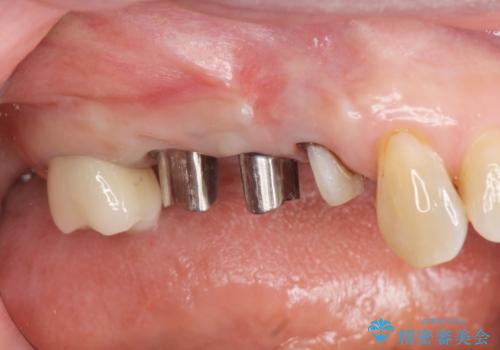

- 「噛むと歯に痛みを感じる、噛めない。」、と痛みの改善を希望され来院されました。

X線写真検査を行ったところ、ブリッジ支台の歯が破折(割れている状態)し抜歯が必要な状態です。

抜歯をしたのちしっかりと咬合力を回復し前後の歯を守るためにも、入れ歯やブリッジではなくインプラントによる咬合機能回復を計画します。